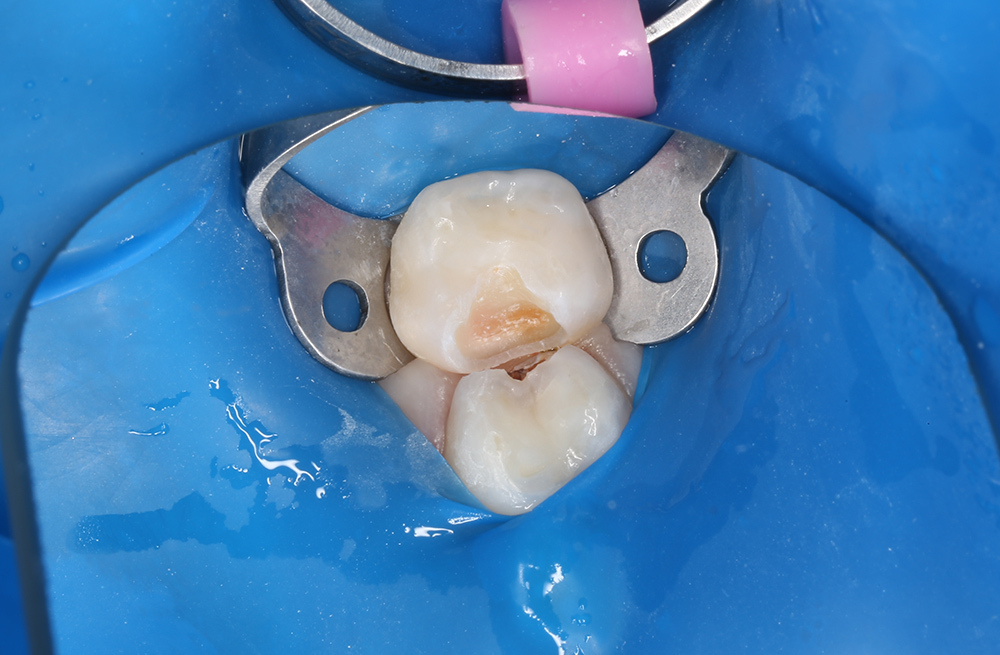

Диагностика и лечение скрытого кариеса на постоянном зубе у семилетнего ребёнка